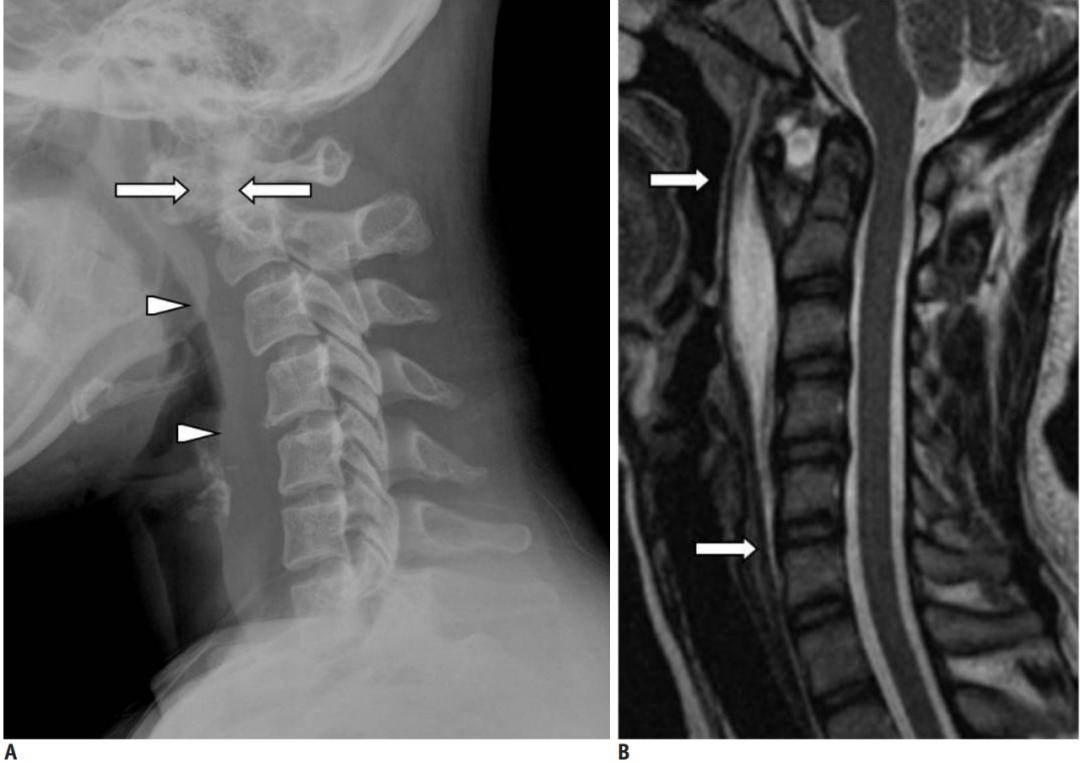

明确诊断主要通过影像学方法,颈椎CT是关键。 颈长肌钙化性肌腱炎特异性的影像表现是C1-4椎体前缘软组织肿胀和积液与C1椎体前弓下方不规则钙化沉着共存。

颈椎侧位片能够显示上颈椎前纵韧带和颈长肌组成的软组织影增宽,密度增高,正常时宽度为3-4mm,急性炎性水肿时可增宽到1cm以上,并可显示椎前软组织内的钙化影,一般位于C1-2水平 。此外,还可见颈肌痉挛引起的颈椎前凸消失。颈椎侧位平片所见的发育性寰椎前弓的下方附属小骨片、寰椎前弓的撕脱骨折以及茎突舌骨肌韧带的钙化极易与本病所见的钙化混淆。

CT的高分辨率能够明确肌腱内的钙化,能够明确是钙化而不是其他骨骼来源的高密度影。 钙化一般位于寰椎前弓的下方和枢椎齿状突的前方,少部分可位于下颈椎前侧 。CT有助于明确椎体前积液的存在和排除其他病理表现,如骨折或脓肿。MRI对诊断不是必须,但有时可帮助确定软组织异常,排除咽后脓肿,脊椎炎或肿瘤。 MRI检查T2加权在椎前可见局限性的裂隙样区域,大多位于C1-4水平,呈高信号改变,这反应是由于炎症引起的积液 。T2加权、脂肪抑制序列和T1加权对鉴别积液和脂肪组织、含脂肪的骨髓以及咽后感染、脊椎炎有重要作用。MRI检查在钙化检查方面存在不足,T2加权呈低信号。

30岁女性,诊断为颈长肌钙化性肌腱炎,但钙化位于不寻常的位置:C4-5椎间隙前侧。A:颈椎侧位片示寰枢椎半脱位(长箭头)和椎前软组织肿胀(无线箭头);B,C和D:颈椎MRI示C1-6椎前软组织肿胀伴积液,D示齿状突骨侵蚀(无线箭头)

上述病人,E为增强,F为抑制像,G和H:经非甾体抗炎药治疗3天后查颈椎CT示C4-5椎前无定形钙化。